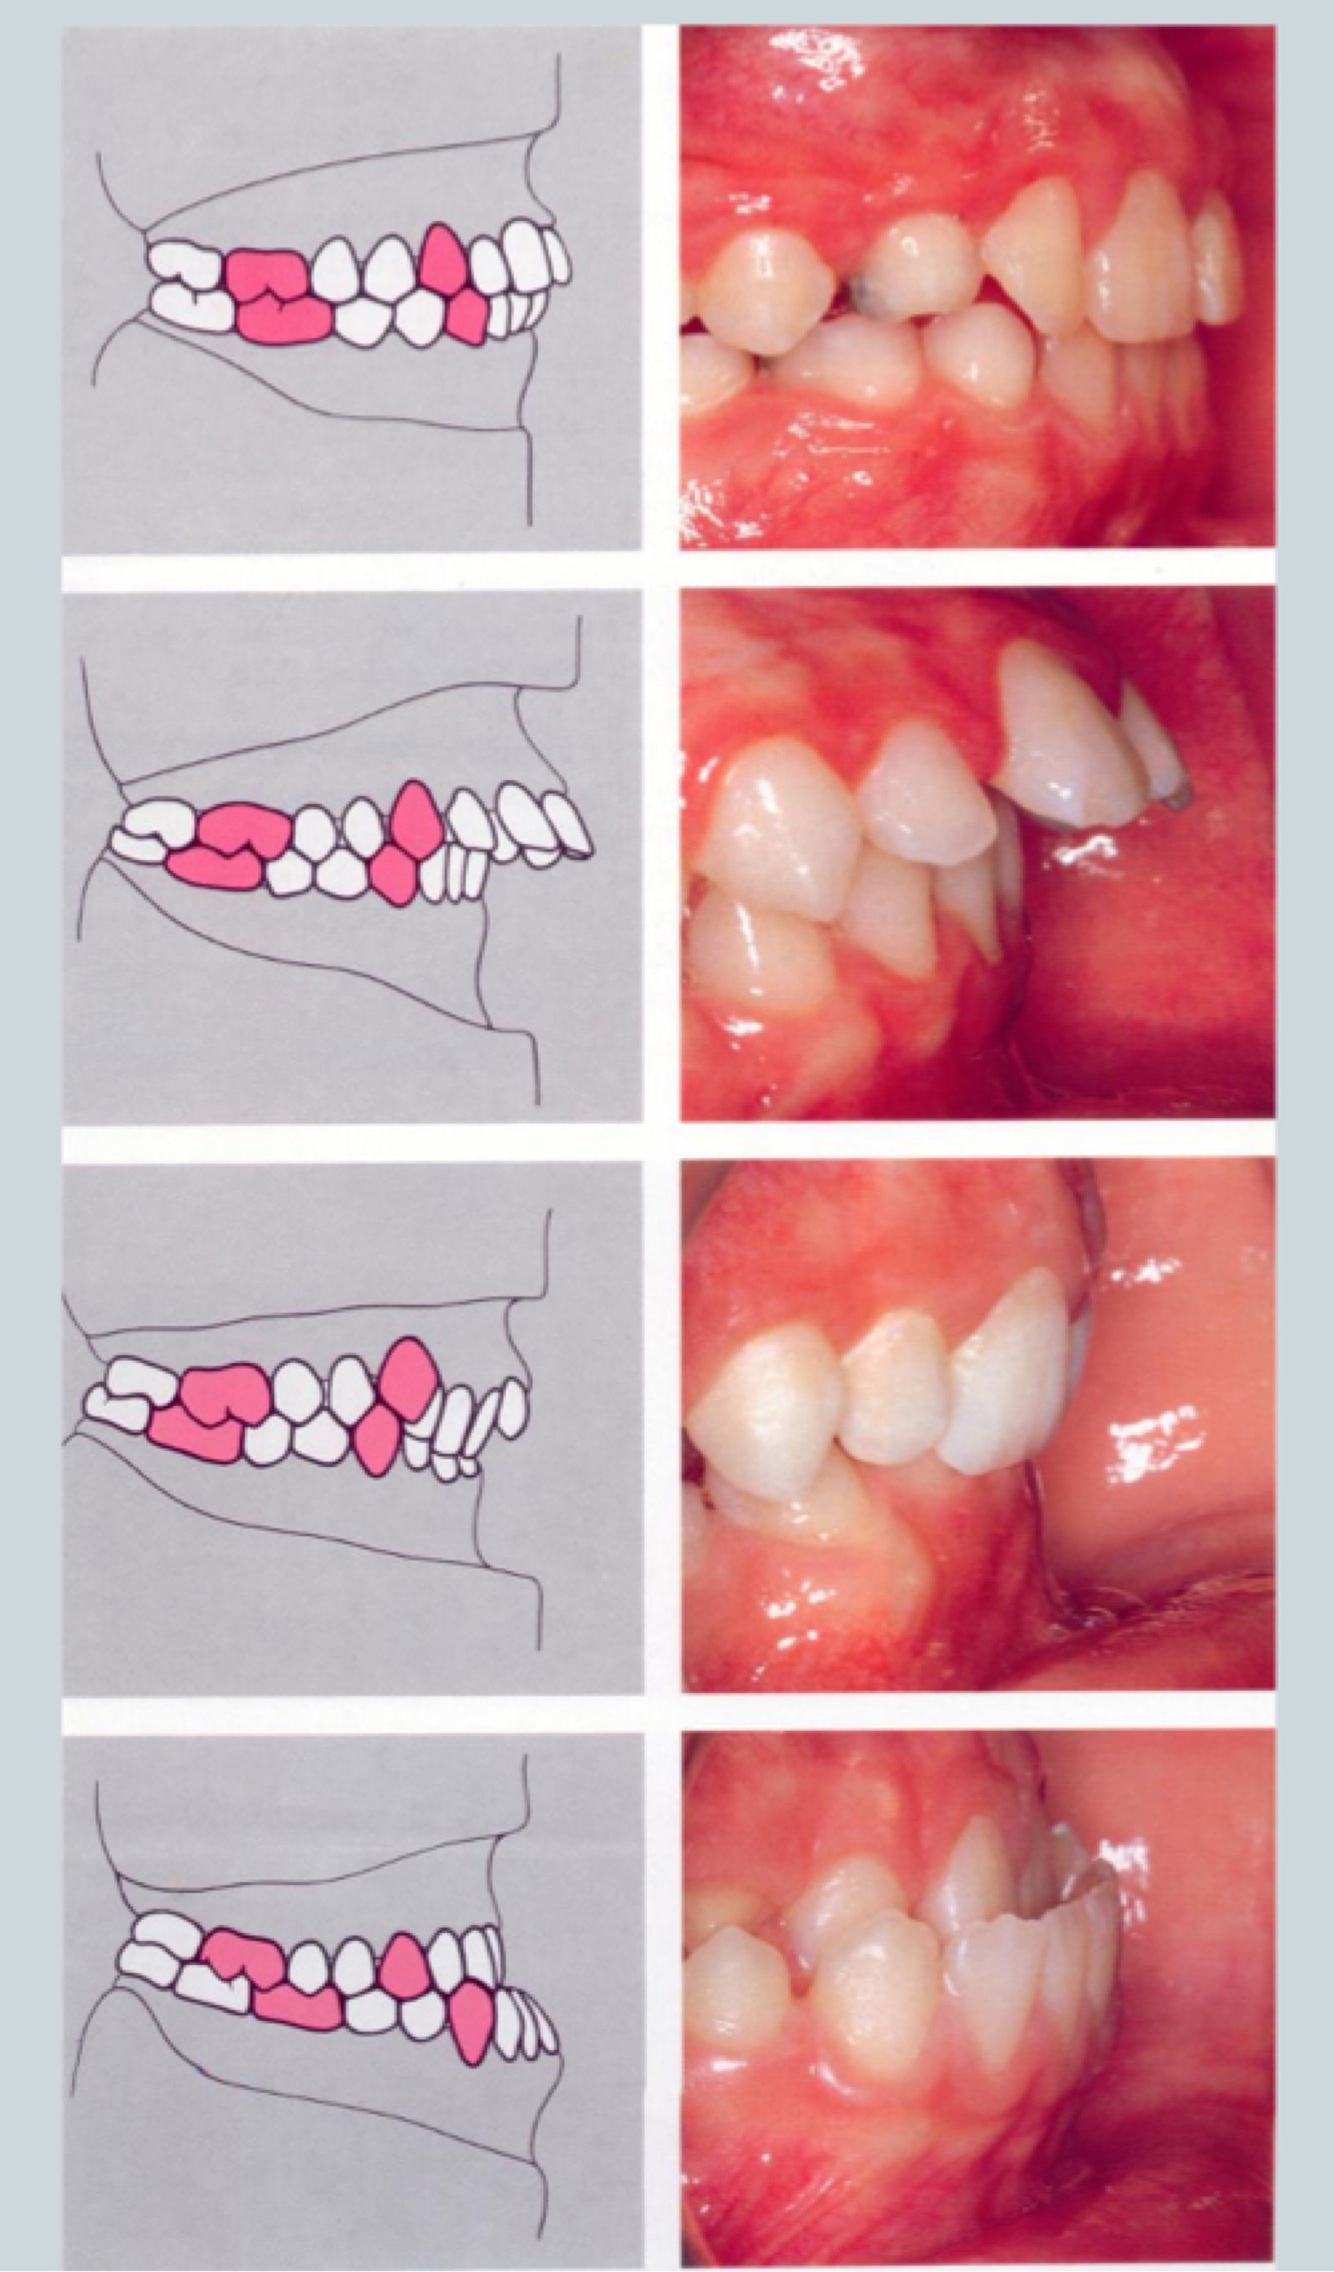

Aetiology : Soft Tissue

Soft tissue influence depends on:

A

• Skeletal

• AP and vertical

• Lips

• Length

• Tone

• Activity

• Swallowing pattern

20

Q

Aetiology: Soft Tissue

Clinical assessment of soft tissue:

Left to right pics:

1. Mild class II - overjet mild

2. More class II - greater overjet

3 - tight lower lip - leading to retroclination of lower incisors and so overjet is increased

But when you look at facial profile they dont look as if they’re different in terms of AP skeletal relationship